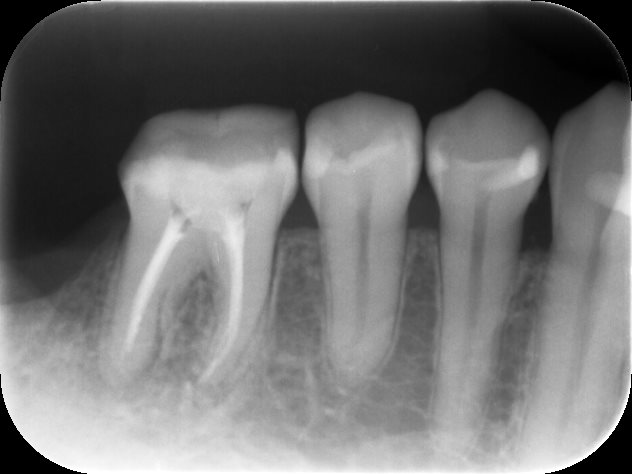

神経の治療完了時のレントゲン

根管治療が完了し、痛みも落ち着いたため、被せ物の作製へ進みました。